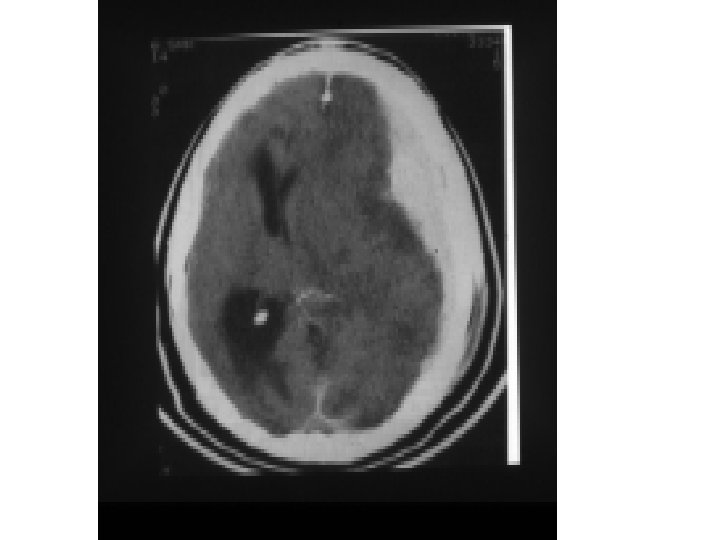

Subdural Hematom (SDH) • • Travma sonrası parenkim laserasyonu Yüzeyel veya asıcı venlerin kopması BT’de konkav görüntü Başvuru sırasında nörolojik tablo EDH’a göre daha kötü • Mortalite çok daha yüksek % 50 -60’lara kadar çıkabilir

Hızlı büyüyen kontüzyon